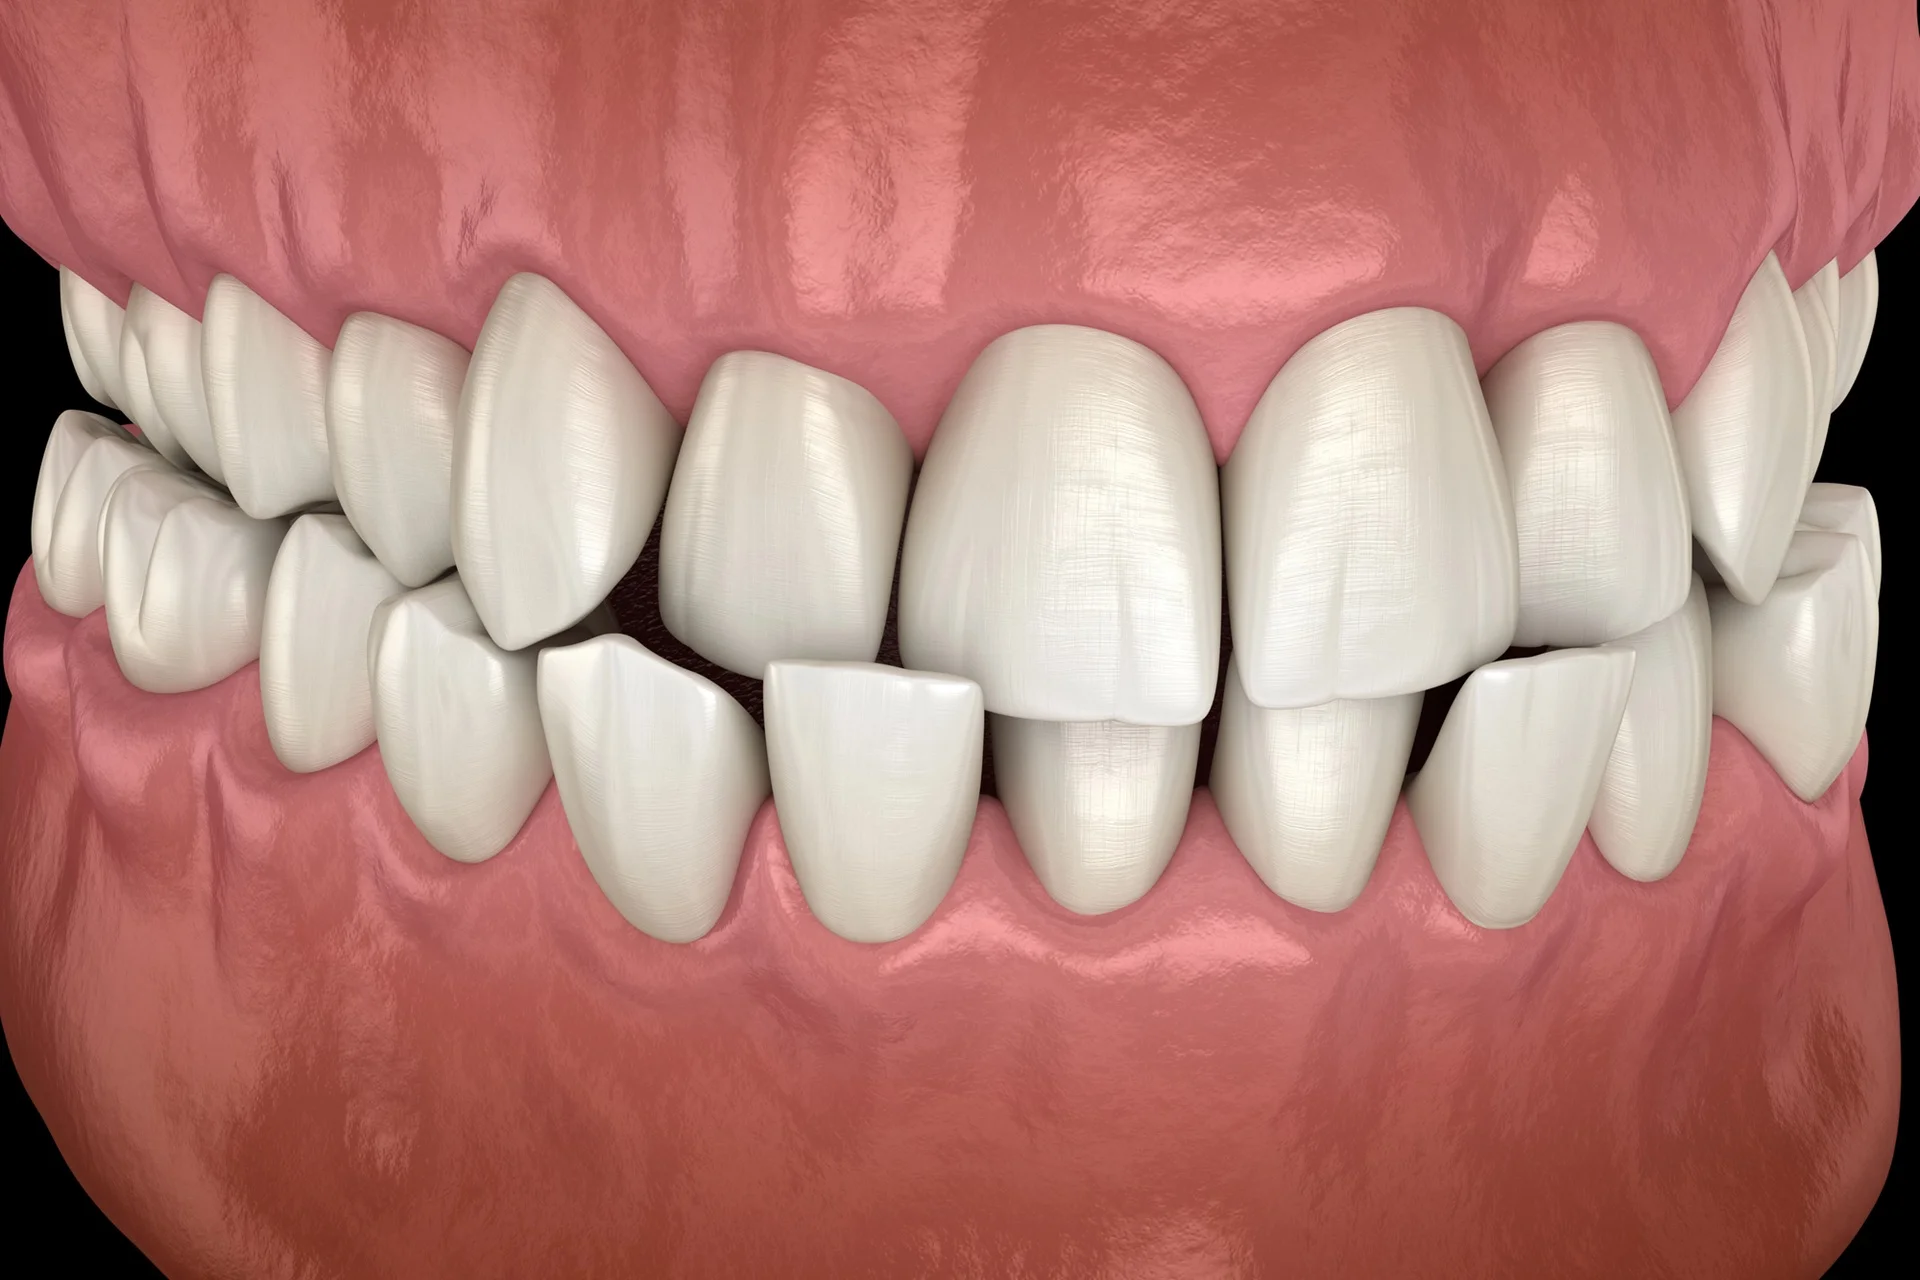

Zgryz krzyżowy to wada zgryzu, w której dolne zęby lub dolna szczęka wysuwają się na zewnątrz poza górne – ale w kierunku bocznym, nie do przodu. Prawidłowo, przy zamkniętych zębach, górne zęby boczne powinny zachodzić na zewnątrz na dolne. Przy zgryzie krzyżowym ta relacja jest odwrócona: dolne zęby boczne stoją na zewnątrz, górne wewnątrz.

Rozróżniamy kilka odmian tej wady. Zgryz krzyżowy boczny (tylny) to najczęstsza forma – dolne zęby trzonowe lub przedtrzonowe po jednej albo obu stronach wypadają poza górne. Przy jednostronnym zgryzie krzyżowym żuchwa często ucieka w bok przy zamykaniu – pacjent podświadomie przesuwa szczękę na jedną stronę, żeby znaleźć wygodniejsze ułożenie. Na dłuższą metę powoduje to asymetryczny wzrost kości twarzy.

- Zgryz krzyżowy jednostronny – zęby boczne po jednej stronie; żuchwa ucieka w bok przy zamykaniu, twarz asymetryczna

- Zgryz krzyżowy obustronny – obie strony boczne odwrócone; wąska górna szczęka w stosunku do dolnej

Przy jednostronnym zgryzie krzyżowym żuchwa ucieka w bok przy każdym zamknięciu ust – podświadomie szukamy wygodniejszego ułożenia szczęki. Przez lata prowadzi to do asymetrycznego wzrostu kości twarzy: jedna strona żuchwy rośnie więcej niż druga, twarz staje się wizualnie asymetryczna. U dorosłego bez leczenia w dzieciństwie korekta takiej asymetrii może wymagać chirurgii ortognatycznej.